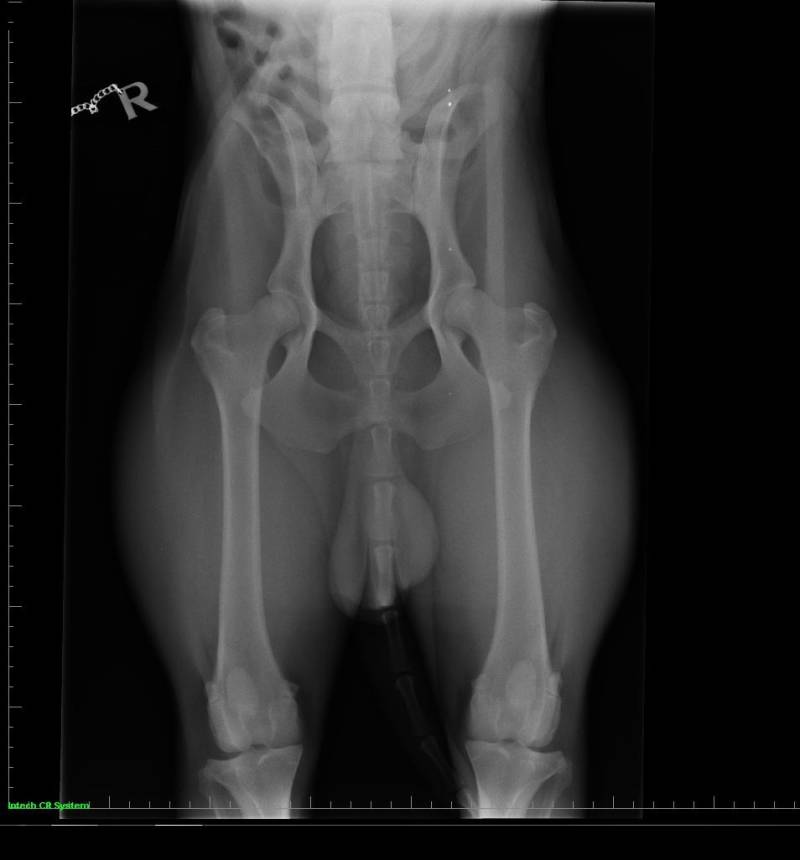

• heupen (kwalificatie A , Norberg L106 R103)

• ellebogen (kwalificatie 0 )